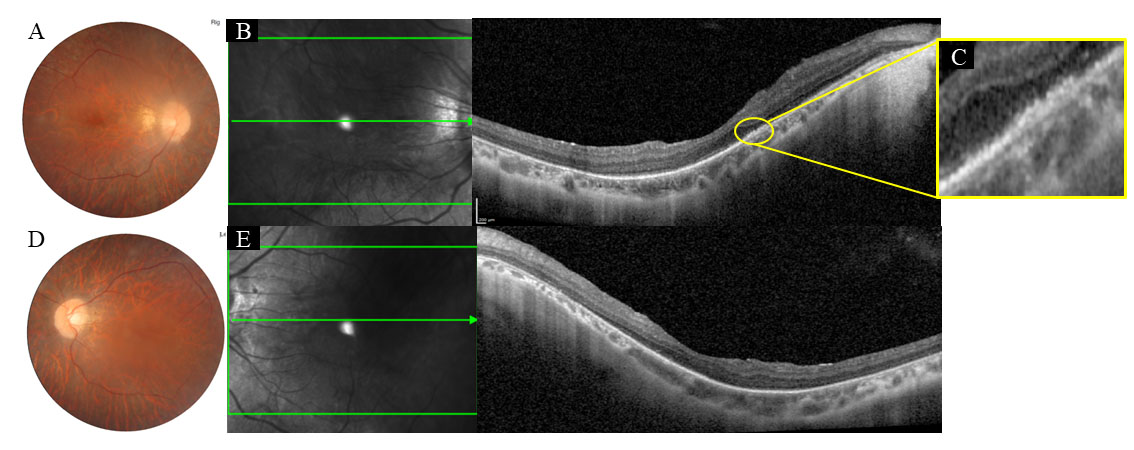

Figure 4. Images of Case 5 with RPE65 gene mutations. Case 5 with mutation c.370CT>C;p.(Arg124*) and c.1022 T>C;p.(Leu341Ser) at age 23 years with fundus (A, D) showing classic retinitis pigmentosa–like features, in addition to myopia features such as tilted disc and peripapillary

atrophy. Optical coherence tomography of both eyes (B, C, right eye and E, left eye) demonstrates disruptions in the ellipsoidal zone, in addition to abnormal curvature of the eye and thin choroid.